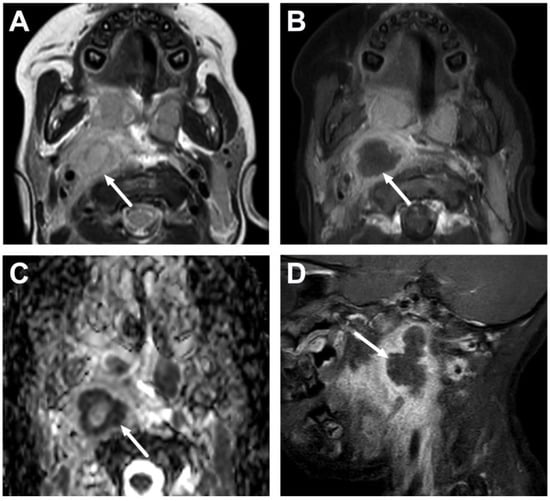

5.1. Lymphadenitis with Purulence vs. Necrosis

5.2. Cystic Masses

| Abscess | T1 SE T2 Dixon (water) DWI post-contrast T1 Dixon (water) | Non-enhancing collection with low ADC values enclosed in abnormally enhancing soft tissue edema. | Detection of an abscess usually requires operative consideration and exact abscess location, and extensions are useful in operative planning. | Abscesses may have an intermediate T2 signal content; blood products and/or postoperative status may complicate abscess assessment; necrotic lymph nodes may be misinterpreted as suppurative lymphadenitis. |

| Cystic masses and potential neoplasms | Whole protocol | Identification of cystic component vs. neoplastic tissue, both with or without signs of infection. | Relevant differential diagnostics; exclusion of findings requiring immediate interventions. | Differential diagnosis may be limited and needs clinical correlation; biopsy may be required. |